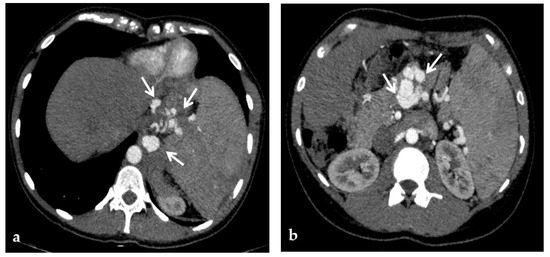

Figure 12.

Anteroposterior view of a percutaneous transhepatic and transsplenic portography imaging series of a chronic complete extrahepatic portal vein thrombosis with portal cavernous transformation in a 17-year-old boy with a history of gastrointestinal bleeding and portal hypertension after liver transplant for biliary atresia. (a) Percutaneous transhepatic portography shows complete extrahepatic portal vein thrombosis (white arrow), with opacification of an irregular cavernomatous network (black arrow). (b) Opacification of a very tiny fibrotic cord representing the thrombosed portal trunk is seen (arrow). Several attempts to cross the portal vein occlusion failed. (c) Percutaneous transsplenic anterograde portography shows complete extrahepatic portal vein thrombosis and cavernous transformation (arrow) from a different perspective. (d) The tiny residual of the thrombosed main portal trunk (arrow) was easily recognized on the transsplenic superior mesenteric vein portography. (e) Fluoroscopic image shows angioplasty of the main portal vein, performed through a 12-mm non-compliant balloon catheter. The focal notch (arrow) represents the tight anastomotic stenosis that probably led to secondary thrombosis. (f) Fluoroscopic image shows the resolution of the focal notch (arrow) after high-pressure inflation of the non-compliant 12-mm balloon catheter. (g) Control portography shows an expanded main portal vein with improved hepatopetal portal flow, but still with irregular profiles (arrow). (h) Through a hybrid transhepatic and transjugular approach under combined ultrasound and fluoroscopic guidance, the connection between the intrahepatic portal vein and the vena cava was created advancing a 0.018” micro guidewire into the right atrium (arrow). The wire was snared through the right transjugular access providing a through-and-through access for precise transjugular intrahepatic portosystemic shunt (TIPS) placement. The completely image-guided hybrid approach allowed to reduce the attempts of transjugular intrahepatic portal vein puncture. (i) Portography image shows the deployment of two imbricated Viatorr stents to create the TIPS (arrows), with regular intrastent opacification. Despite previous angioplasty, a prestenotic aspect of the main portal vein is seen (black arrow). (j) Portography image shows a self-expandable 9-mm metallic stent placed to cover the main portal vein trunk stenosis (white arrow). Control portography shows regular mesenteric-portal vein opacification with TIPS patency and preserved opacification of intrahepatic portal branches (black arrows); cavernous vessels disappeared.